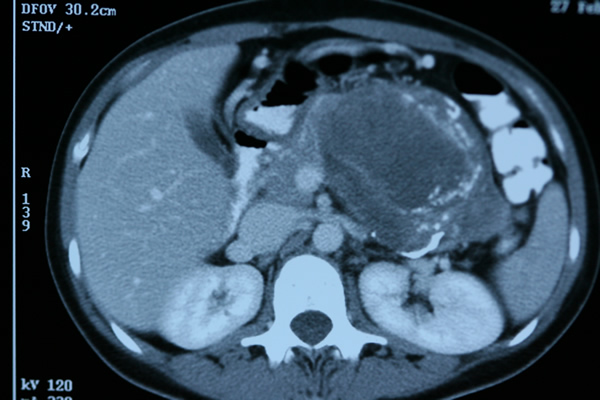

Kalıtsal olmayan risk grubundaki hastalar kronik pankreatit ve pankreas kisti olan hastalardır. Bu hastalar genellikle bilgisayarlı tomografi veya manyetik rezonans(MR) ile görüntülenerek incelenirler. Bunlara ek olarak son yıllarda gerektiğinde endoskopik ultrasonografi de uygulanmaktadır. Kalıtımsal risk grubundaki hastalara da benzer yöntemler uygulanmaktadır.

Bu tarama programlarında amaç erken kanserleri saptamak olduğu kadar kanser öncesi gelişen ve kansere dönüşebilen doku değişikliklerini saptayabilmektir. Genel olarak topluma göre 5-10 kat risk taşıyan hastalarda 50 yaşta bu tarama programlarını başlatmak önerilmektedir.

Risk taşıyan hastalarda tarama programlarında solid lezyon, kist veya PanIN-3 olarak adlandırılan problemler saptandığında cerrahi tedavi koruyucu olarak önerilmektedir.